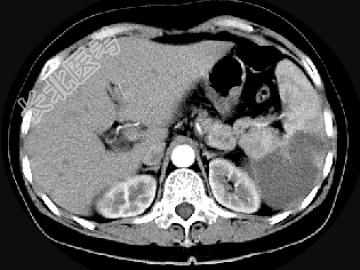

- 单项选择题女,54岁, 左上腹痛,CT检查如图, 最可能的诊断是 ( )

A、脾淋巴瘤

B、脾脓肿

C、脾梗死

D、脾血管瘤

E、脾转移癌